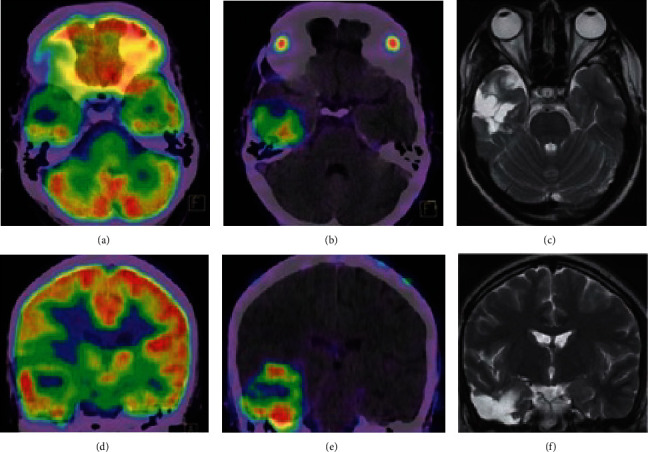

Results: Tissue studies demonstrated PSMA expression in tumor vascular endothelial cells, without expression in normal brain tissue, though the extent and intensity of staining varied by anti-PSMA antibody and methodology. Most included studies reported on gliomas, which showed strong PSMA ligand uptake and more favorable tumor to background ratios than other PET tracers. There are also case reports demonstrating PSMA ligand uptake in prostate cancer brain metastases, nonprostate cancer brain metastases, and meningiomas. We also review the properties of the various PSMA-binding radiotracers available. Therapeutic and theranostic applications of PSMA-binding tracers have been studied, including labeled alpha- and beta-ray emitting isotopes, as well as PSMA targeting in directing MRI-guided focused ultrasound.

Abstract Image